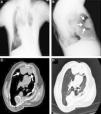

We report the case of a 61 year-old man, with a past history of bronchiectasis and severe restrictive ventilatory defect due to thoracic scoliosis (Figure 1 A), who came to the pulmonology outpatients department with complaints of asthenia over the last year. He was an occasional pipe smoker and the physical examination showed marked thoracic deformity which limited chest expansion. A chest X-ray showed a large retrosternal opacity (Figure 1B) and the chest computed tomography (CT) confirmed the presence of a retrosternal lobulated mass, 10.2 cm × 3.7 cm, in the right hemithorax (Figure 1C and D). A percutaneous CT-guided biopsy was carried out and the histology showed evidence of mesenchymal neoplasm without necrosis, significant pleomorphism or mitotic figures. The tumor cell population stained diffusely for CD 34, vimentin, bcl-2 and CD 99 and negative for S-100. Ki-67 was <5%. Although a benign SFTP was diagnosed based on the histology, a right thoracotomy was performed for diagnosis and treatment. A pedunculated tumoural mass was complete resected with segmental resection of the right upper lobe. Immunohistochemistry showed positivity for CD-34 and bcl-2 confirming SFTP. The pathological examination revealed multiple mitotic figures (12 mitoses per 10 high-power fields), mild pleomorphism, hypercellularity, focal hemorrhage and several areas of necrosis and the resection margins were tumor-free. According to these features the tumor was classified as malignant. The post-operative period was uneventful and the patient was discharged home. The patient is now in the third month after surgery without any sign of local recurrence or metastization.

Figure 1. (A) Chest X-ray showing a marked thoracic deformity; (B) chest X-ray showing a large retrosternal opacity; (C and D) chest CT showing a retrosternal lobulated mass at the right hemithorax with 10.2 × 3.7 cm.